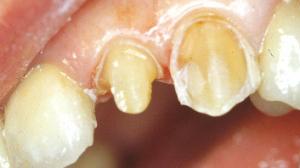

Un premier fil rétracteur fin est inséré. Il écarte légèrement la gencive.

Nous descendons la limite cervicale jusqu’à " effleurer " le fil sans toucher la gencive avec la fraise.

A aucun moment de la préparation la fraise ne doit toucher la gencive !

Les limites de préparation sont actuellement juxta-gingivales.

Un deuxième fil rétracteur plus gros est inséré au dessus du premier. La gencive est de nouveau repoussée par ce deuxième fil.

La limite cervicale est encore descendue avec la fraise congé. La fraise "effleure " ce second fil sans toucher la gencive.

Lors de l'empreinte, le deuxième est déposé, la limite se retrouve alors légèrement sous-gingivale. Le premier est laissé en place pour assurer l'hémostase (cette technique permet d'obtenir une limite sous-gingivale sans toucher la gencive avec la fraise).